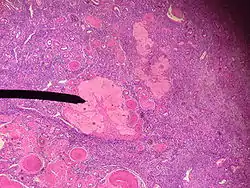

The corpus albicans (Latin for "whitening body"; also known as atretic corpus luteum, corpus candicans, or simply as albicans) is the regressed form of the corpus luteum. As the corpus luteum is being broken down by macrophages, fibroblasts lay down type I collagen, forming the corpus albicans. This process is called "luteolysis". The remains of the corpus albicans may persist as a scar on the surface of the ovary.

The corpus luteum normally grows to about 1.5 centimeters in diameter, reaching this stage of development 7 to 8 days after ovulation. Then it begins to involute and eventually loses its secretory function and its yellowish, lipid characteristic about 12 days after ovulation, becoming the corpus albicans.[1] In the ensuing weeks, this is replaced by connective tissue and over months is reabsorbed.[2]